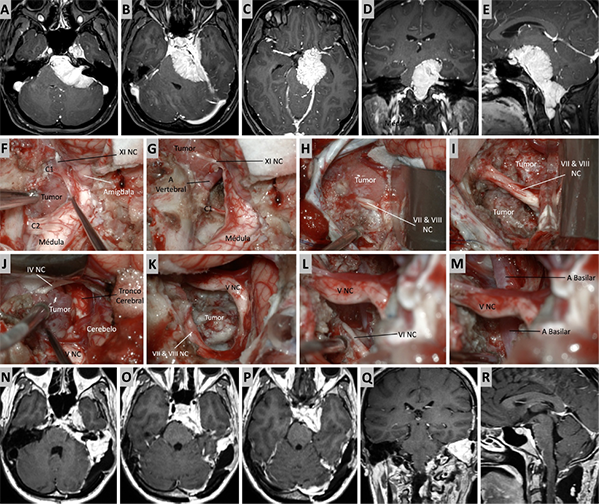

Figura 10. Caso ilustrativo #8. MRPC con implantación petroclival con invasión con extensión a la fosa media, clivus inferior, agujero magno y región premedula. Paciente con anacusia izquierda. A. Se observa un corte axial. MPC con extensión al ángulo pontocerebeloso y compromiso del CAI. B. Se observa extensión del tumor a la fosa media, seno cavernoso y ala mayor del esfenoides. C. Se observa extensión del tumor a ala menor del esfenoide, cisterna silviana y optocarotidea.D-E. Extensión del tumor a la fosa media, al clivus inferior y a la región premedular. Se realizo un abordaje presigmoideo acompañado de un abordaje far-lateral y un abordaje retrosigmoideo. F. Se observa la porción tumoral ubicada en el foramen magno y la región premedular, fue necesario un abordaje far-lateral. G. Resección completa de la porción ubicada en foramen magno y región premedular. H. Porción tumoral que se extiende desde clivus inferior a clivus medio. I-J. Resección de tumor de clivus medio e inferior. K. Porción tumoral en clivus superior con extensión a fosa media. Se realizo un abordaje transpetroso anterior para esta región. L-M. Resección casi total. N-R. Imágenes postquirúrgica que muestran una resección casi total.